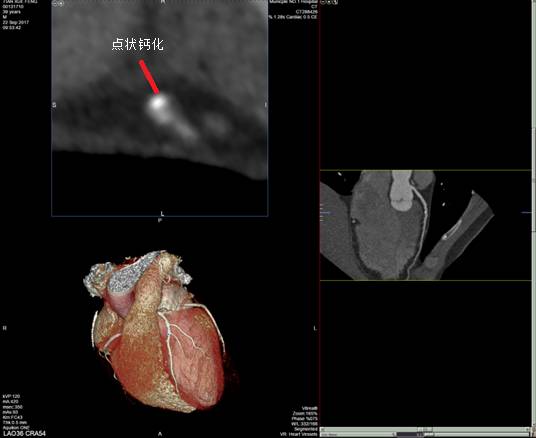

■ 冠脉探针

通过冠脉探针可以显示管腔横截面,以便更好的观察斑块形态。通常在VR项可以显示探针的位置,以此点为中心,向上、向下各显示7个断层,每个断层1 mm,加上所选取的一层,共显示15 mm长的冠状动脉管腔横截面,冠脉探针与CPR相结合,能更精确的判断冠脉管腔狭窄程度。而探针显示的某个特点也可以初步判断斑块的稳定性,如点状钙化、指环征等。